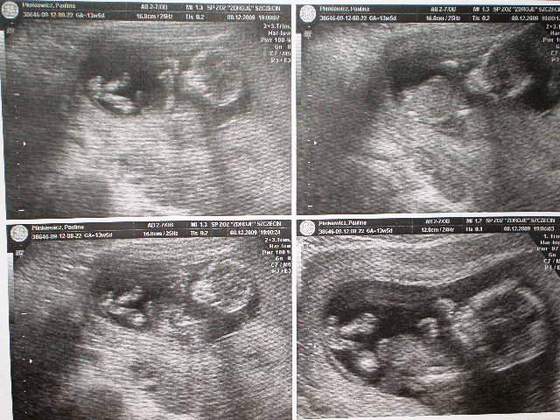

Wklejam moją kruszynkę z wczorajszego USG - ma 4 cm, serduszko bije, to 11 tc. tak się cieszę, jeszcze niedawno myslałam, że to naprawdę niemożliwe.